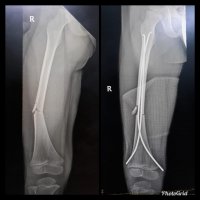

TITANIUM ELASTIC NAILING (TEN)

Titanium Elastic Nailing (TEN) is intended for fixation of diaphyseal fractures of long bones where the medullary canal is narrow or flexibility of the implant is paramount. The biomechanical principal of the Titanium elastic nailing is based on the symmetrical bracing action of two elastic nails inserted into the metaphysis, each of which bears against the inner bone at three points. The complication rates associated with Titanium elastic nailing have been reported to be minimal.